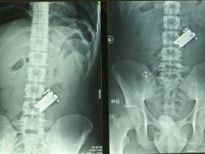

Çin'de yaşayan bu yaşlı adamın karısından çektiğini hiçbir erkek çekmemiştir herhalde. 66 yaşındaki Lin'in eşi, kumar ve alkol alışkanlığından şikayet edip duruyordu. Bir gün adam çok alkollüyken kafasına çivi bile çaktı.